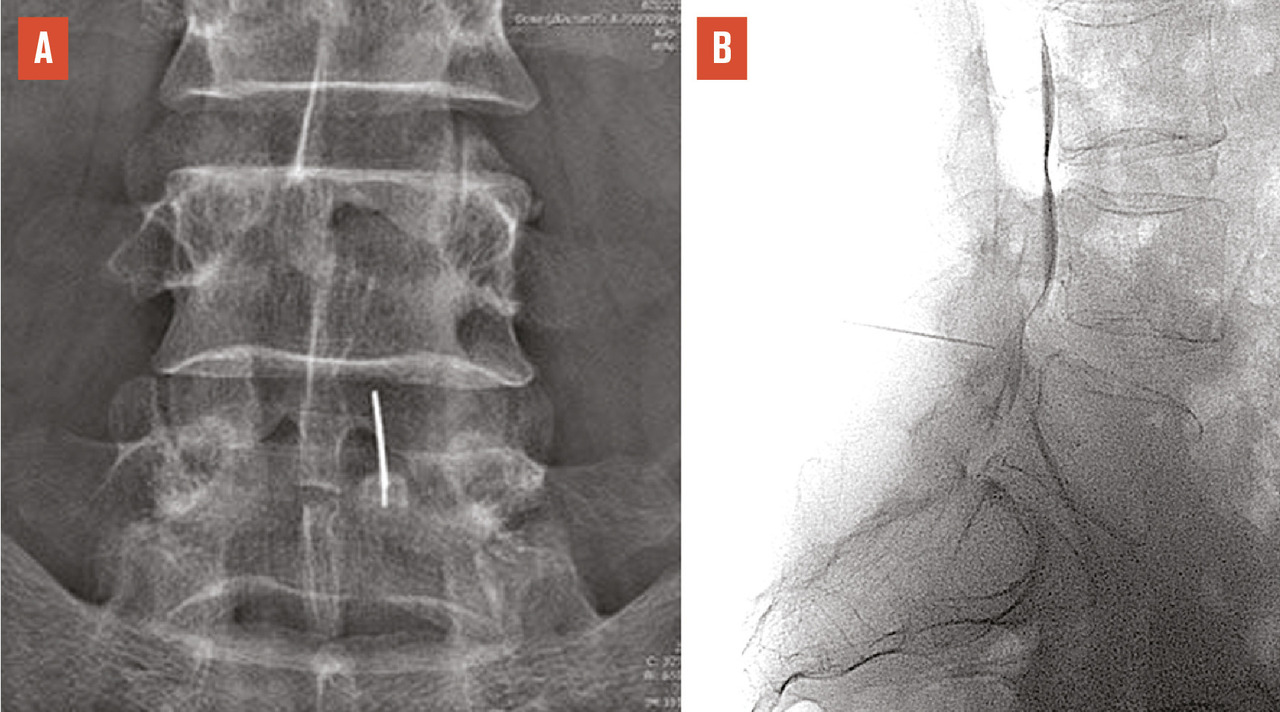

Le plus souvent, les fractures ostéoporotiques consolident et les douleurs peuvent être gérées par le ­traitement médical avant de disparaître spontanément en quelques semaines. Dans certains cas cependant, la pérennisation des douleurs requiert des morphiniques et contraint le patient à un alitement prolongé, avec les risques inhérents chez une personne âgée. La fracture peut aussi se majorer progressivement, ce qui peut entraîner une perte importante de hauteur du corps vertébral et majorer la cyphose. Parfois encore, chez le sujet âgé, la fracture ne consolide pas et une véritable pseudarthrose, avec image de « vide » (gaz) intrasomatique se constitue, source de douleurs mécaniques et d’évolution prolongée. On peut alors observer, sur les radiographies et en scanner, une image cavitaire ­linéaire intracorporéale qui peut contenir du gaz (fig. 5), ainsi qu’un signal liquidien en IRM.

L’objectif d’une cimentoplastie ­percutanée (vertébroplastie et kyphoplastie à ballonnets) est double : antalgie et lutte contre la cyphose et le déséquilibre rachidiens. La vertébroplastie percutanée (fig. 5) consiste à injecter par voie transpédiculaire, dans le corps vertébral fracturé, un ciment acrylique (polyméthylmétacrylate) qui est de même nature que celui que l’on utilise pour sceller les prothèses ­articulaires, et dont la tolérance ­biologique est bien établie. Dans la cyphoplastie (ou kyphoplastie) à ­ballonnets (fig. 7), l’injection est précédée d’une tentative de réexpansion du corps vertébral fracturé, grâce à des ballonnets gonflables afin de regagner une partie de la hauteur perdue et de réduire la cyphose.

L’objectif premier de ces deux techniques est antalgique. Consolider le corps vertébral et soulager les patients invalidés par des douleurs, intenses et persistantes, permet leur remise en charge et la prévention des complications du décubitus. Dans les cas favorables, la consolidation de la fracture et la diminution des douleurs permettent au patient de retrouver une mobilité. La consolidation de la fracture joue un rôle particulièrement important dans les fractures pseudarthrosées avec « vide intrasomatique » (fig. 5). La ­vertébroplastie et la kyphoplastie permettent aussi d’éviter que la fracture progresse (fracture en deux temps) et que l’angle de cyphose ­augmente, ce qui est fréquent. Elles réduiraient aussi la surmortalité associée aux fractures vertébrales.23